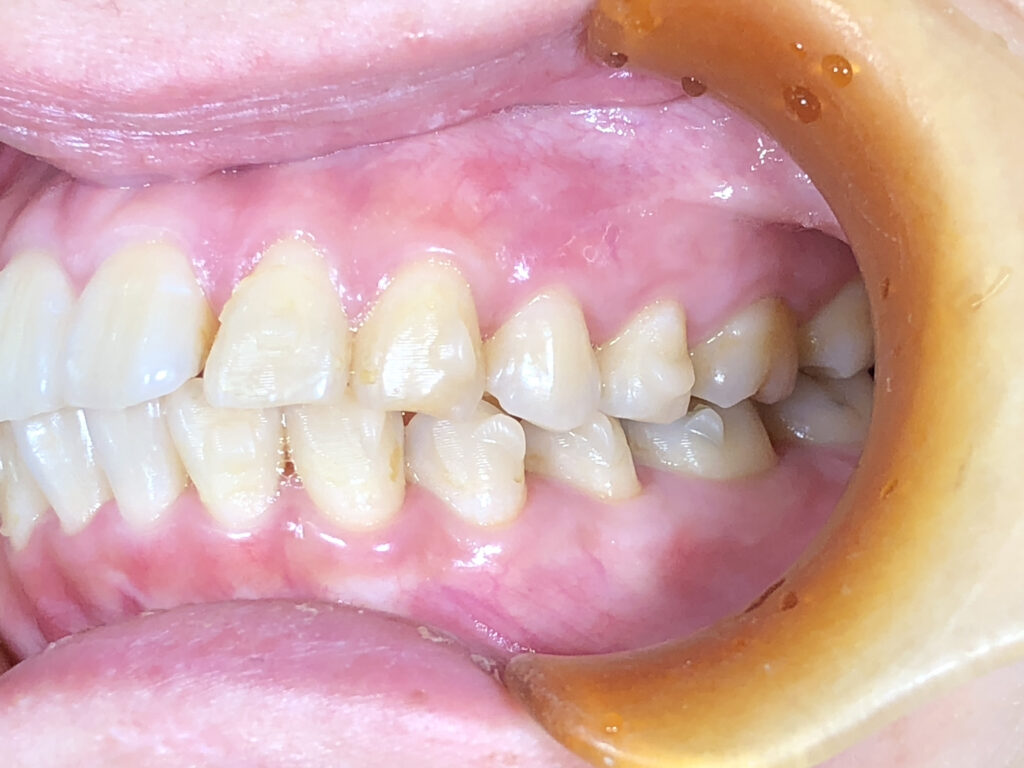

オーバージェット

治療前

治療後

患者様は前歯の隙間と歯の向きを主訴として来院されました。前歯の隙間は審美面だけでなく、発音や食べ物の停滞にも影響しやすい状態でした。また、下顎前歯部に歯石が付きやすいことは、歯列不正により清掃不良部位が生じていることが一因と考えられました。 インビザライン矯正では、前歯の角度と位置を適切にコントロールし、隙間を閉じて調和のとれた歯列に整えました。同時に下顎前歯の叢生を改善することで、歯石の付着しやすい環境を改善し、将来的な歯周病リスクの低減にもつながる治療計画としました。下顎はもう少し改善可能と説明したところ、十分満足とのことで、治療終了としました。 |